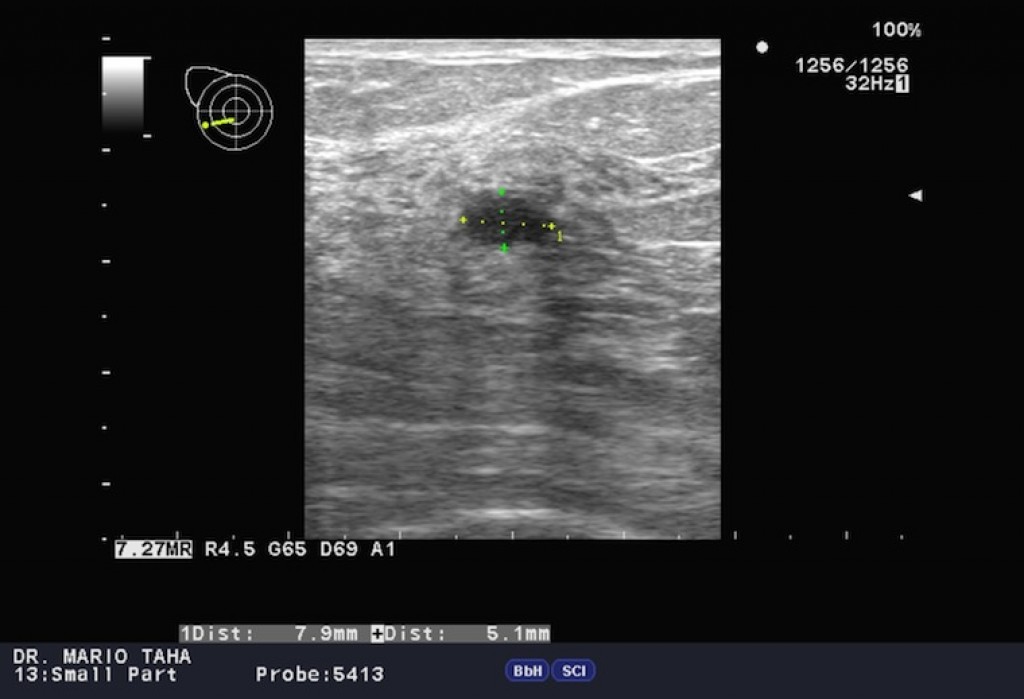

Фото рожистого воспаления на груди в зоне реконструкции молочной железы (сопровождается лихорадкой до 39 градусов, болью как при ожёге) . Фото красного пятна на груди при мастите - смотрите ниже на этой странице . УЗИ мастита .

УЗИ молочных желез выявило разлитой ретромаммарный абсцесс, множественные секвестры в области верхне-наружного и нижне-наружного квадрантов, абсцесс в области верхне-наружного квадранта 5х6 см . После биопсии этого абсцесса было получено гнойное . . .